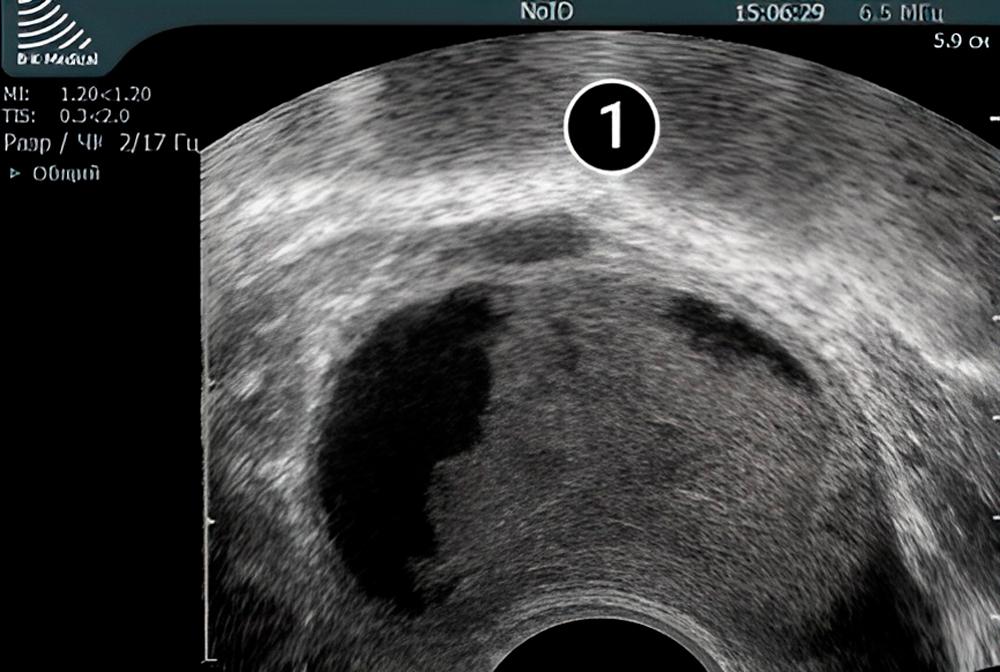

Lo que se puede ver en el ultrasonido/ecografía

En la imagen de abajo, el útero redondeado es claramente visible. En su interior se puede ver el saco amniótico rodeado por el endometrio. El saco amniótico es el óvalo oscuro con contornos claros, ubicado en la parte inferior del útero, la que se considera una de las posiciones óptimas para el saco.

En la etapa actual del embarazo, el saco amniótico todavía es muy pequeño, entre 5 y 7 mm.